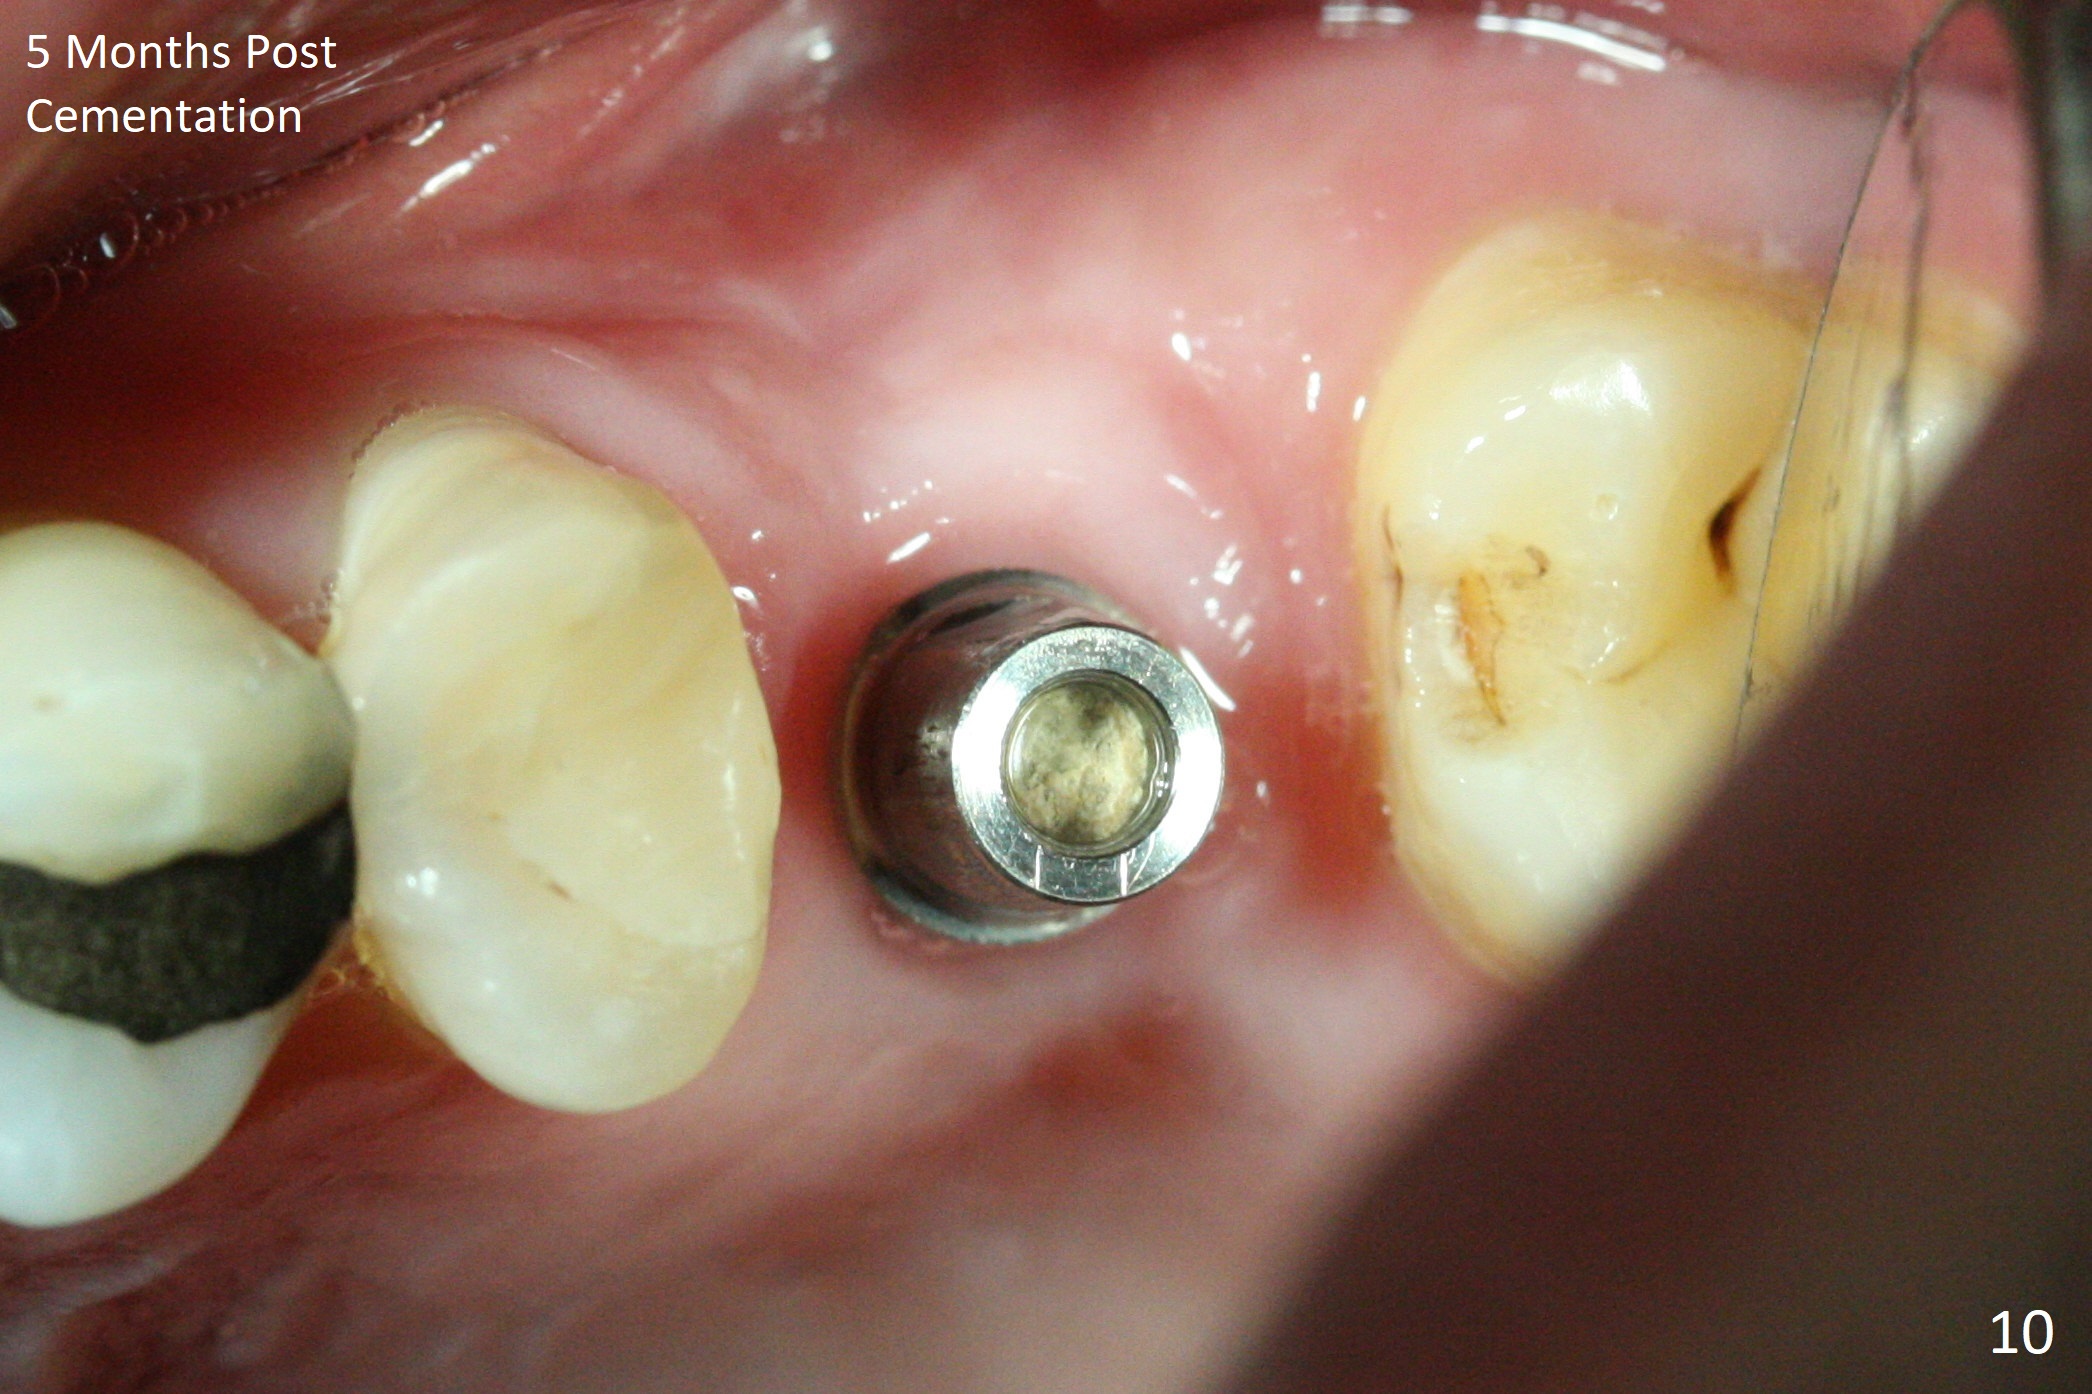

After extraction of the distobuccal residual root of the tooth #14 (Fig.1 arrow), the gingiva around the socket does not look like the keratinized one (Fig.2 *). An osteotomy through the distobuccal socket would seem too buccal for immediate implant. The palatal gingiva feels too tough to be stretched. An incision is made (Fig.3 dashed line); with elevation, the thick flap is transferred buccally (curved arrow). An osteotomy is initiated in the palatal bone with 1.5 mm drill, followed by Magic Expanders until 4.3 mm for 11 mm (Fig.4,5). Following Magic Drill 3.8x13 mm, the sinus membrane is found to be perforated. The latter is repaired with Osteogen plug. A 4.5x9 mm IBS implant is placed with 50 Ncm (Fig.6). Osteogen plug and allograft (Fig.7 *) are inserted into the remaining distobuccal socket (reduced after bone expansion). When a 5.5x4(4) mm abutment is placed, the transferred flap appears to be adapted to the distobuccal defect (Fig.8 *). Later one suture is placed for fixation. After provisional insertion, periodontal dressing is applied. Nine days postop, the periodontal dressing dislodges. When the loose provisional is removed for recementation, the flap seem to have healed (Fig.9 *). The gingiva heals around the abutment 5 months postop (Fig.9); the distal socket appears to heal while the bone graft remains at the crest (Fig.11,12). When #30 develops buccal abscess, the patient masticates on the left, leading to loss of composite at #13 (Fig.14); in fact the abutment at #14 is incompletely seated.